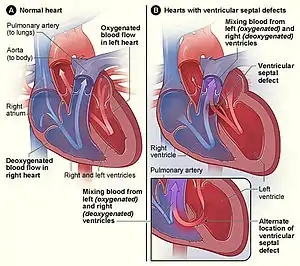

- Holoprosencephaly has been reported in some people with ring 18.[5] This is due to the deletion of the TGIF gene on the short arm of chromosome 18 in some people with ring 18.[6]Approximately 30-40% of people with ring 18 have a congenital heart anomaly. Septal defects are the most common type of defect reported in this population.